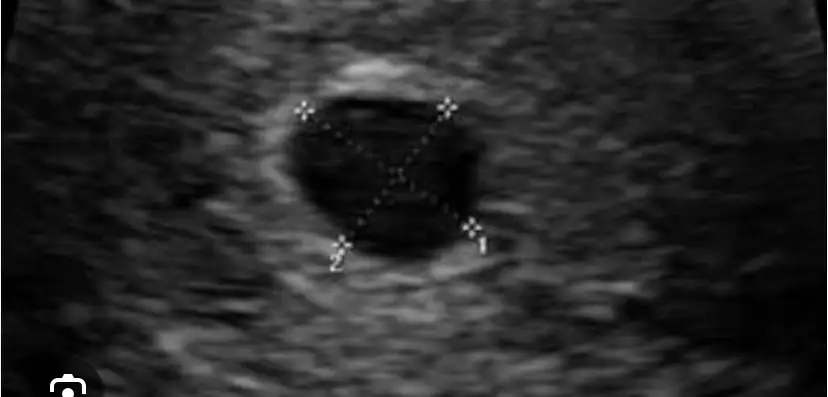

Doktor birşey söylemedi mi bununla ilgli? çatlamadan kalan ve kiste dönüşen bir kist olabilir. Bu ay bende de var 2,5 cm.Kızlar dün doktora gittim 7si çatlama görmüştüm vajinal usgde rahimde böyle boşluk gördü adetime 5 gün var daha kan <2 çıktı böyle durum yaşayan var mı acaba birşey olsa çıkarmıydı kanda.Eki Görüntüle 3562434